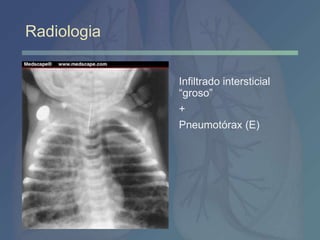

Infiltrado intersticial

“groso”

+

Pneumotórax (E)